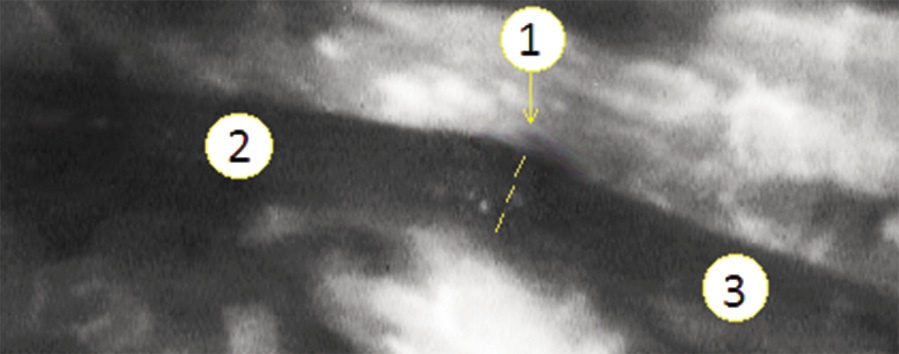

Выполнение ангиографии после основного хирургического приема — выполнения микрохирургического эпиневрального шва — позволяет оценить сохранность и, что не менее важно, эффективность кровотока. Как правило, выполнение эпиневрального шва неотъемлемо сочетается с необходимостью натяжения нервов с целью преодоления диастаза. Последнее, в свою очередь, ведет к транзиторному нарушению кровоснабжения нервного ствола. Так, на интраоперационных ИЦЗ-ангиограммах отчетливо визуализируется зона обрыва контрастирования, вызванного частичным тромбозом сосудов, что является реакцией на продолжающееся кровотечение из культей нерва. Несмотря на это, отмечается сохранение кровотока в интраневральных магистральных сосудах, доходящих практически до линии шва. С течением времени отмечается восстановление кровотока, что проявляется контрастированием более мелких сосудов. Это, в свою очередь, позволяет судить о сохранении эффективного кровотока как в проксимальном, так и в дистальном отрезках нерва (рис. 4).

Рис. 4. ИЦЗ-ангиограмма ствола срединного нерва после наложения эпиневрального шва: 1 — проекция линии микрохирургического эпиневрального шва; 2 — проксимальный отрезок срединного нерва; 3 — дистальный фрагмент срединного нерва / Fig. 4. ICG-angiogram of the median nerve trunk after epineural suture: 1 —projection of the microsurgical epineural suture line; 2 — proximal segment of the median nerve; 3 — distal fragment of the median nerve

Интраневральные сосуды являются одними из важных анатомических ориентиров для точного сопоставления фрагментов поврежденного нервного ствола. Ориентация на сосуды, проходящие в эпиневрии, позволяет избежать перекручивания культи нерва по оси и способствует более точному соприкосновению пучков нервных волокон. Таким образом, интраоперационная ангиография после выполнения эпиневрального шва может рассматриваться и как способ контроля качества его выполнения.

Нарушение кровоснабжения нерва на ИЦЗ-ангиограммах проявляется отсутствием контрастирования его сосудов на фоне активного контрастирования прилежащих мягких тканей. При этом в случае выраженного рубцового процесса в зоне оперативного вмешательства возможно снижение интенсивности кровенаполнения и в мягких тканях. В случае избыточного натяжения на линии шва, частичного тромбирования магистральных сосудов нерва отмечается нарушение адекватного кровоснабжения нервного стола. Например, на рис. 5 представлен случай микрохирургического эпиневрального шва локтевого нерва, выполнение которого сопровождалось натяжением отрезков нерва.

Рис. 5. ИЦЗ-ангиограмма ствола локтевого нерва после наложения эпиневрального шва, отсутствие адекватного кровоснабжения: 1 — проекция линии эпиневрального микрохирургического шва; 2 — дистальный отрезок локтевого нерва; 3 — проксимальный отрезок локтевого нерва / Fig. 5. ICG-angiogram of the ulnar nerve trunk after epineural suture, lack of adequate blood supply: 1 — projection of the epineural microsurgical suture line; 2 — distal segment of the ulnar nerve; 3 — proximal segment of the ulnar nerve

Отмечается лишь незначительное контрастирование интраневрального магистрального сосуда только в проксимальном сегменте на удалении 2 см от места шва. С учетом данных выполненной ИЦЗ-ангиографии было принято решение распустить эпиневральные швы и закончить операцию межпучковой аутопластикой.